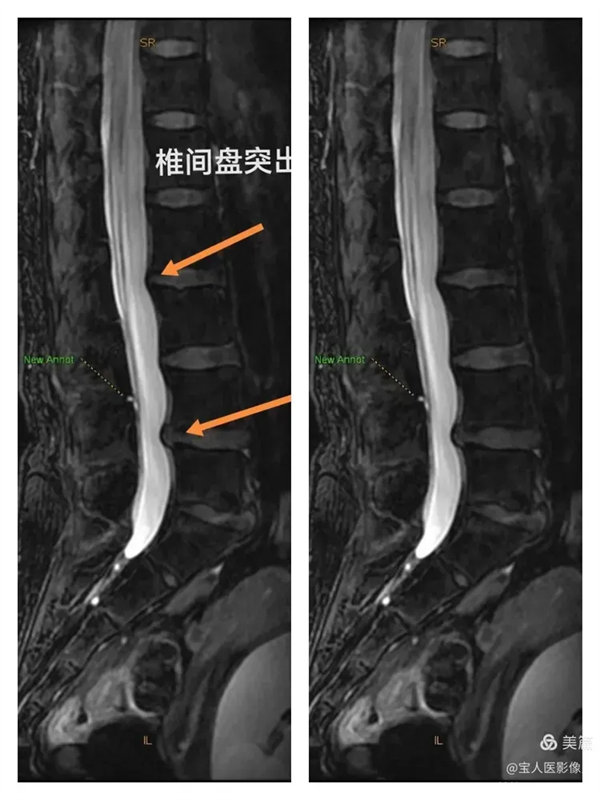

最大密度侧面图,显示腰段硬膜囊内脑脊液(高信号)。

最大密度侧面图,显示腰段硬膜囊内脑脊液(高信号),前方的椎间盘受压弧形凹陷,后方的局部膨出。